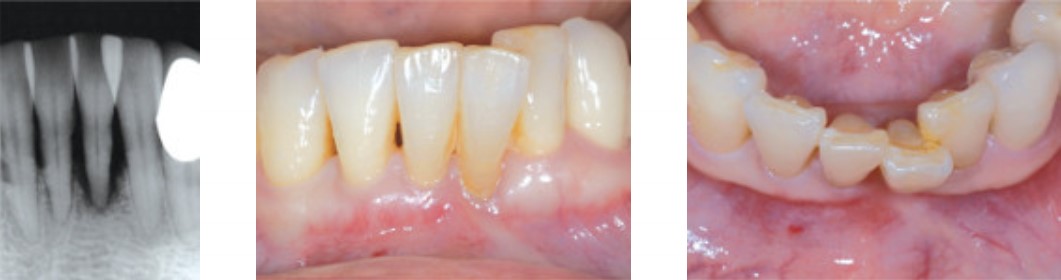

Панорамный снимок и фотография ротовой полости

Экстракция, #41 Имплантат для узкого гребня MS